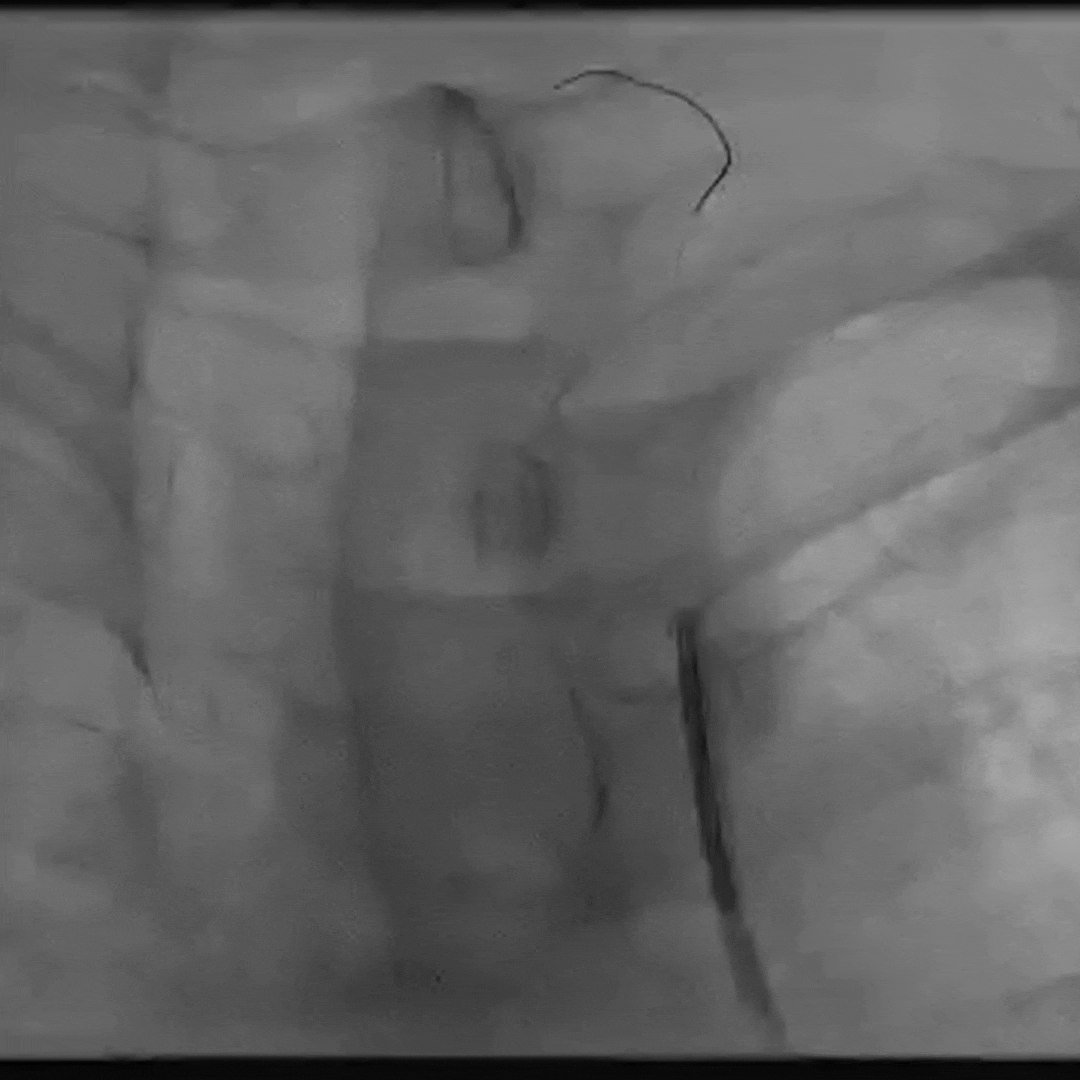

更换Supracore导丝,使用雅培 5*40mm Armada35 球囊扩张后在闭塞起始部植入8*29mm Omnilink支架。

使用雅培 Command导丝顺利超选进入左椎V2段,冠脉3.0*12mm球囊进行扩张,在V18导丝的支撑下,在左侧椎动脉起始部植入一枚雅培4.5*15mm Herculink支架。支架植入后,造影提示椎动脉狭窄得到明显改善。

本例患者为症状性左侧锁骨下动脉闭塞,左侧椎动脉起始部重度狭窄。因左侧肱动脉搏动微弱,锁骨下动脉闭塞近端有残端,导引导管有着陆点,考虑可先行正向开通。术中选用了雅培Omnilink及Herculink两款球扩支架放置于左侧锁骨下与椎动脉起始处,两款支架定位精准,钴铬合金的材质既保证了高径向支撑力也提供了足够的可视性,支架薄壁的设计能够最大化管腔面积,很好地顺应血管解剖,有着极佳的血管成型效果。